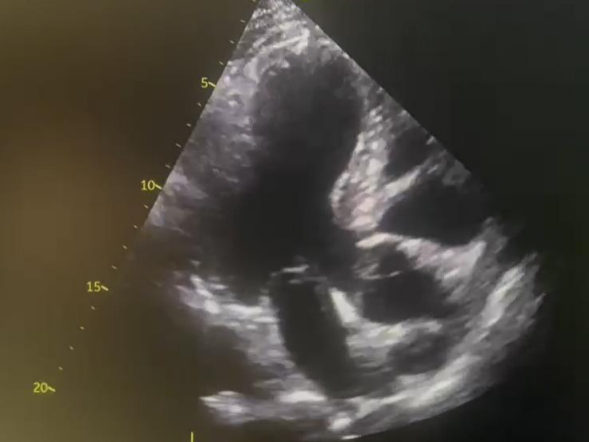

Despite electrolyte optimization, ventricular arrhythmias persisted, and he experienced bradycardia episodes( Figure 2,3). An echocardiogram( Figure 4) revealed cardiac abnormalities, including an aneurysmal basal posterolateral segment, akinesis in various segments, and a reduced ejection fraction. Cardiac MRI (Figure 5) was subsequently performed and showed a wide-necked out pouching from the basal anterolateral and inferolateral left ventricular wall. This was associated with myocardial thinning, severe dyskinesia, and near transmural sub-endocardial late gadolinium enhancement, resembling ischemia more than sarcoidosis.

Figure 4 Transthoracic echo (TTE) showing an aneurysmal basal posterolateral segment.

Figure 5 Cardiac MRI (CMR) showing outpouching from the basal anterolateral and inferolateral left ventricular wallwith associated myocardial thinning, severe dyskinesia and near transmural sub-endocardial late gadolinium enhancement.